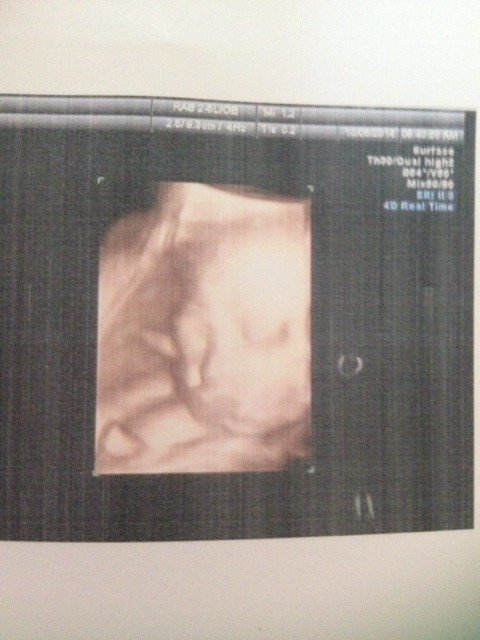

大家帮我看看,这是我今天做的四维彩超,仔细看宝宝嘴巴,我担心像兔唇,宝妈们帮我看看像不像 点击展开 萱萱艾宝 2014-10-08 22:42 为您推荐: 其他回答 指导意见,你好 ,孩子这个思维的检查还是很清晰的,不必担心,如果是有你担心的这个情况,临床的医生就是会直接和你说的,所以不存在这个问题 野鸭子7205 2014-10-15 09:45 相关问题 我想问一问医生这种情况宝宝需要吃药吗??我家宝今天出生21天了 嘴巴从下生就发干 在他十几天的时 今天不知怎么了,嘴巴苦得很,嘴唇也是黑色的,可我也没吃什么啊,有宝妈像我一样的吗? 请问宝宝前天和昨天嘴巴里面烂了,但是昨晚好了今天中午她爷爷给她两口鱼吃,会不会又犯了吧!我很但心